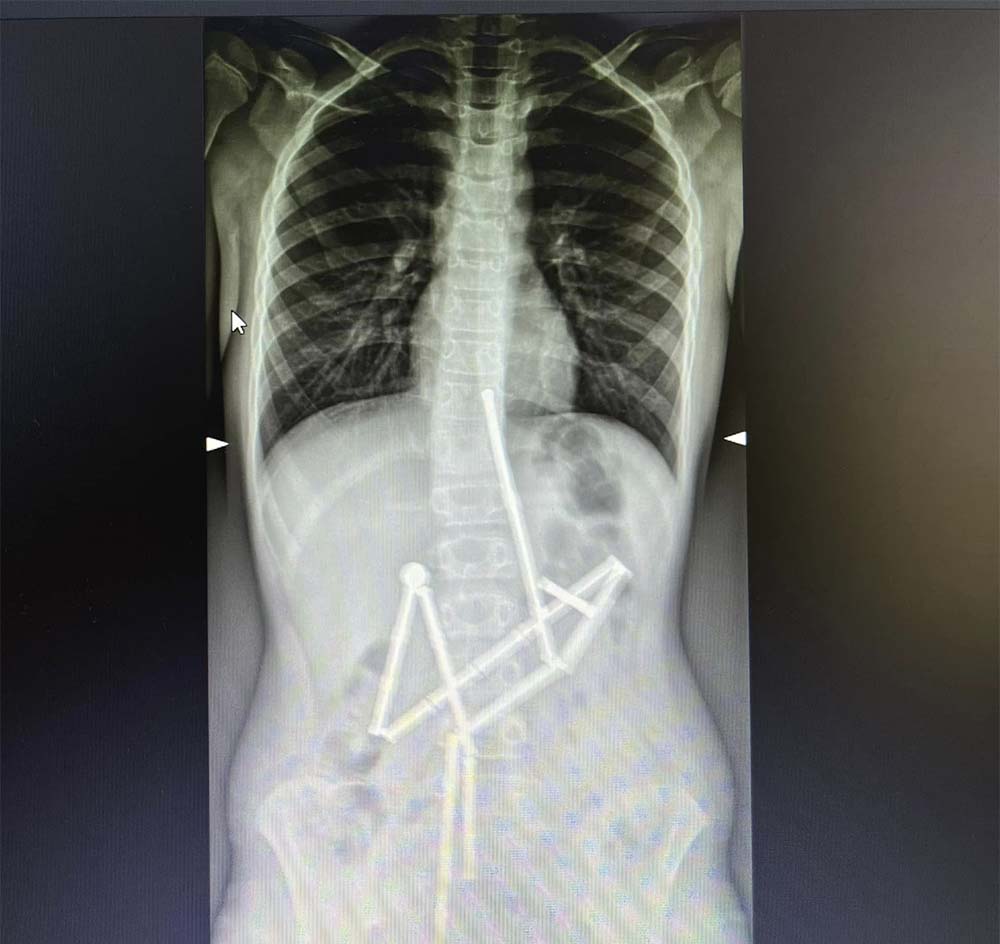

Вже на першому рентген-знімку побачили в травному каналі цілу групу сторонніх тіл, з яких вдалося впізнати магнітний конструктор. 20 магнітів знаходились у різних частинах шлунково-кишкового тракту, проте були зʼєднані між собою, йдеться на Фейсбук-сторінці лікарні.

Консиліум прийняв рішення про невідкладне оперативне втручання, адже кожна година очікування могла погіршити стан пацієнта. Відмінність магнітів від інших сторонніх тіл, які можуть проковтнути діти, полягає у їх притягненні один до одного та защемленні тканин.

Медикам вдалося захопити перший магніт і витягти його разом із ланцюжком з 18 елементів конструктора. Проте один магніт залишився й спеціалісти не мали змоги видалити його ендоскопічно. Надалі за операційним столом почали працювати хірурги. В дитини було виявлено 5 перфоративних отворів та останній елемент конструктора. Всі отвори були закрито, а магніт видалено.